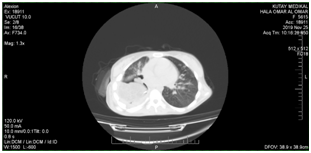

• Follow up after one month; the PT has a very good general condition, chest CT revealed that the previous residual cavity has fulfilled with the omentum except a small a dead space Figure E1.

E1 15-12-2019